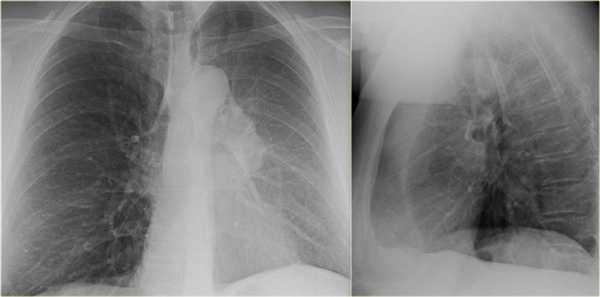

- Минимальное уменьшение объема легкого без подъема левого купола диафрагма.

- В загрудинном пространстве визуализируются изменения высокой плотности, которые спавшейся верхней доли левого легкого.

- Корень левого легкого патологичен, что может соответствовать образованию, обтурирующее просвет бронха.

- Выше перечисленные находки наводят на мысль, что это ателектаз верхней доли левого легкого.

На КТ снимках синей стрелкой указан долевой ателектаз, а красной стрелкой опухоль, которая обтурирует левый верхний долевой бронх (центральный рак легкого.

Ателектаз верхней доли левого легкого с типичным симптомом воздушного серпа (Luftsichel sign — luft(air)+sichel(sickle)), обусловленный гипервентиляцией верхнего сегмента нижней доли левого легкого на фоне коллапса верхний доли левого легкого. Гипервентилируемый

сегмент визуализируется на прямой рентгенограмме от дуги аорты до апикальной части легкого.

- В левом легком патологические изменения высокой плотности с потерей силуэта контуров сердца.

- Высокое стояние диафрагмы левого легкого.

- Смещение вниз косой щели.

- Низкое расположение правого корня легкого.

Данные изменения характерны при тотальном ателектазе верхней доли левого легкого и частичный ателектаз правого легкого. Так контуры сердца справа хорошо визуализируются то, можно сказать, что частичный ателектаз не средней доли, а нижней доли правого легкого.

Оцените нижележащие ПЭТ/КТ изображения. Легочная карцинома обтурирующая левый верхнедолевой бронх и правый верхнедолевой бронх. Множественные метастазы в кости. Стрелкой указан метастаз в ребро.

Симптом воздушного серпа (luft sichel sign) — это симптом, который возможно встретить на рентгенограмме органов грудной полости при ателектазе верхней доли левого легкого.

Изменения на рентгенограмме обусловлены гипервентиляцией верхнего сегмента нижней доли левого легкого, который смещается к сзади и кверху, и тем самым располагается между коллабированной долей легких и средостением. На фронтальной рентгенограмме сегмент визуализируется от дуги аорты до апикальной части левого легкого.

На рентгенограмме представлен тотальный коллапс верхней доли левого легкого. Обратите внимание на высокое стояние левого корня легкого. Спавшаяся верхняя доля левого легкого расположено позади грудины. В данном случае компенсаторная гипервентиляция нижней доли левого легкого повлияло на то, что позиция диафрагмы и средостения в норме.